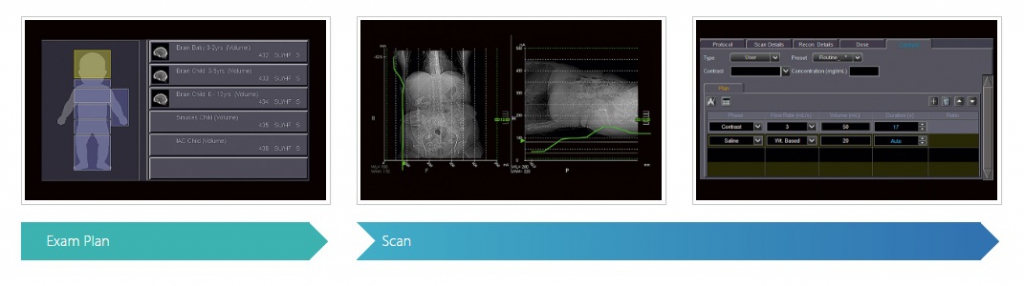

Система обеспечивает упорядоченный рабочий процесс от установки пациента до диагностики. Быстрое и эффективное обследование с автоматическим выбором дозы обеспечивает как оптимальные результаты визуализации, так и опыт пациента.

Выбор процедуры

После регистрации пациента Aquilion Lightning автоматически выбирает правильные процедуры для взрослых или детей.

Контроль дозы

Aquilion Lightning помогает гарантировать, что предел дозы облучения, определенный вами, не может быть превышен, чтобы избежать непреднамеренных высоких доз.

Управление контрастностью

Позволяя добавлять протоколы контраста в план диагностики, скорость потока и объем автоматически зависят от фактического веса пациента и типа диагностики, а инъекция синхронизируется со сканированием.

Оптимизация клинического рабочего процесса

Aquilion Lightning разработан для удобной работы с загруженными рабочими нагрузками. Интуитивный пользовательский интерфейс системы поможет вам шаг за шагом пройти через диагностику с использованием современных и понятных графиков и анимаций. Множество интеллектуальных функций обеспечивают быстрый и эффективный рабочий процесс.